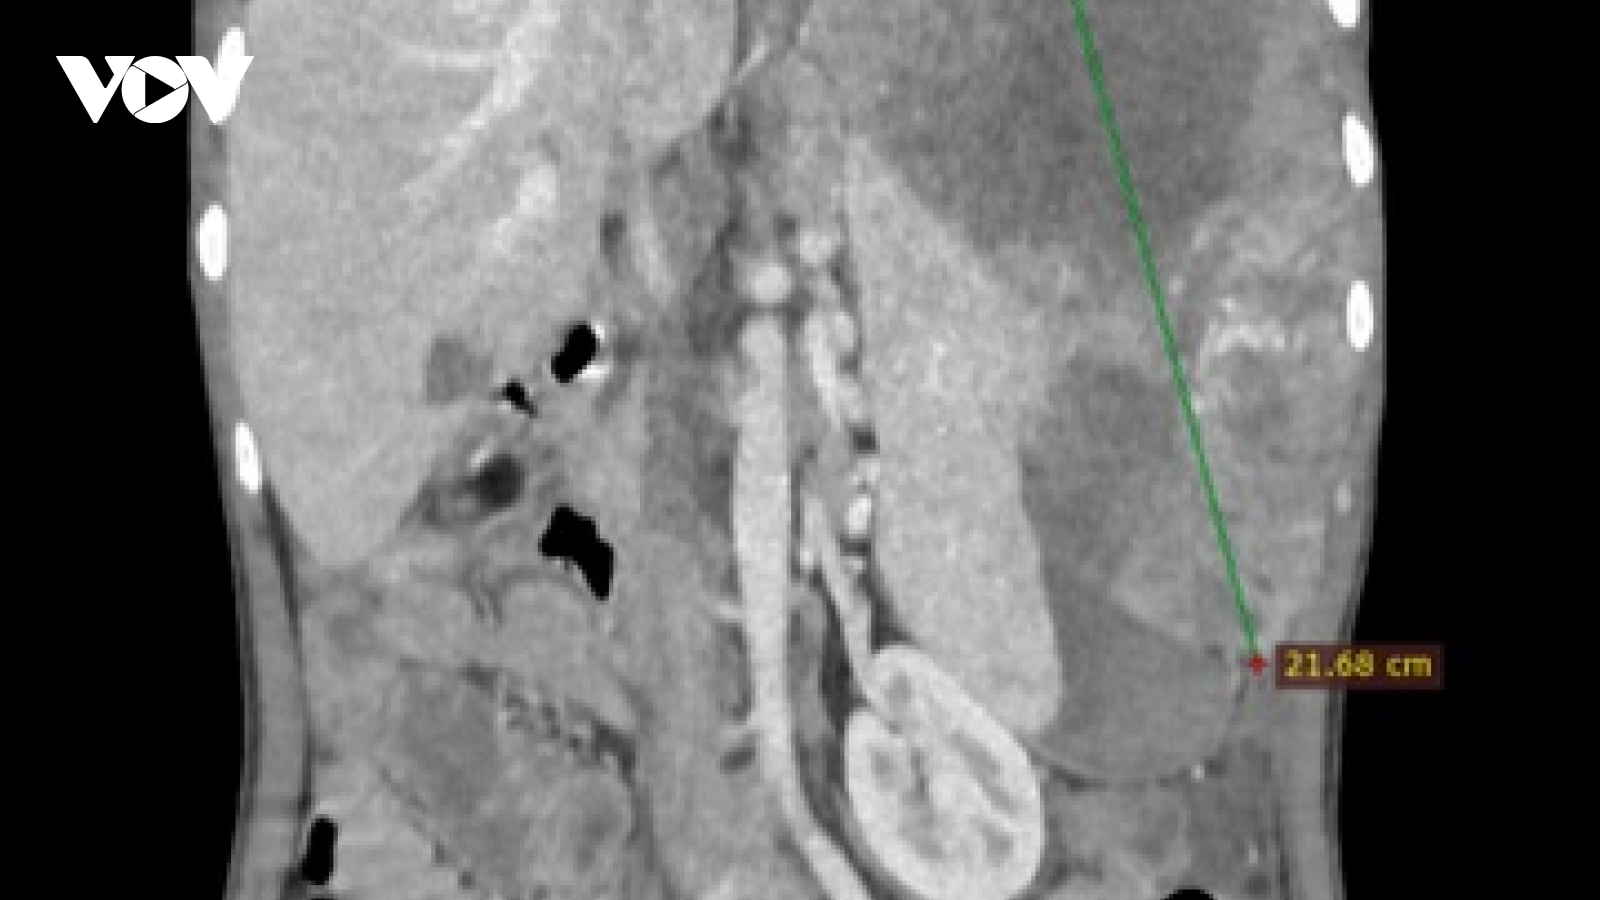

Ung thư gan: Sát thủ thầm lặng với tỷ lệ tử vong cao

VOV.VN - Ung thư gan là căn bệnh tiến triển âm thầm, đa số phát hiện muộn, khiến việc điều trị gặp nhiều khó khăn. Câu chuyện của chàng trai 25 tuổi thoát chết sau ca đại phẫu cho thấy sự khốc liệt của căn bệnh này.